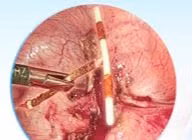

Sống trong khổ sở vì tình trạng tiểu mất kiểm soát suốt 8 năm, người đàn ông đã hết tiểu rắt, ngủ ngon giấc nhờ phẫu thuật holep điều trị tăng sinh tuyến tiền liệt. Đây là kỹ thuật cao tiên tiến, tối ưu trong điều trị tuyến tiền liệt.